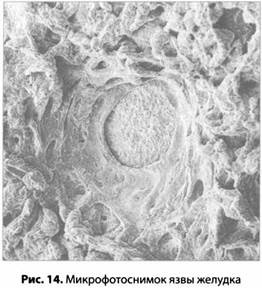

Наконец мы добрались до медицинской проблемы, с которой начался путь теории стресса к славе и богатству. Язва — это дыра в стенке органа (рис. 14). Если язва возникает в желудке или в окружающих его органах, это называется язвенной болезнью. Язву, возникшую в самом желудке, называют язвой желудка; язву, расположенную немного выше желудка, называют язвой пищевода, а если она возникла на границе между желудком и кишечником, ее называют язвой двенадцатиперстной кишки (или дуоденальной язвой). Это самое распространенное из всех язвенных заболеваний.